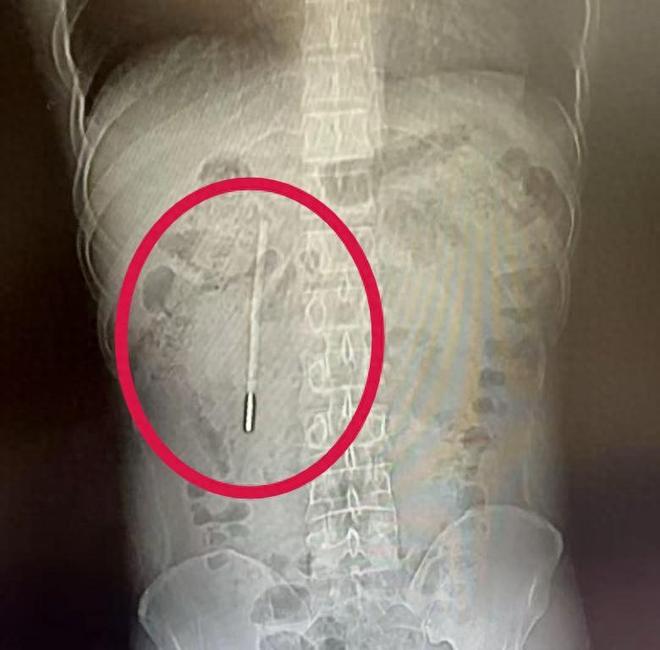

浙江温州,一个32岁的男人,因为肚子不舒服去医院做CT。医生盯着屏幕看了半天,脸色变了——

这根体温计是他12岁时误吞的。20年7000多个日夜,它就那么“藏”在他身体里,前端紧紧抵着肠壁,随时可能刺破血管,引发大出血、肠穿孔。

医生说,那根体温计的前端已经紧紧抵在肠壁上,随时可能导致穿孔、大出血。幸好最后通过内镜手术取出来了,体温计除了刻度磨没了,外观完好,水银没有泄漏——这是极端的幸运。20年,他赌的是命。让他走上这张赌桌的,不是什么大不了的事,就是四个字:害怕被骂。